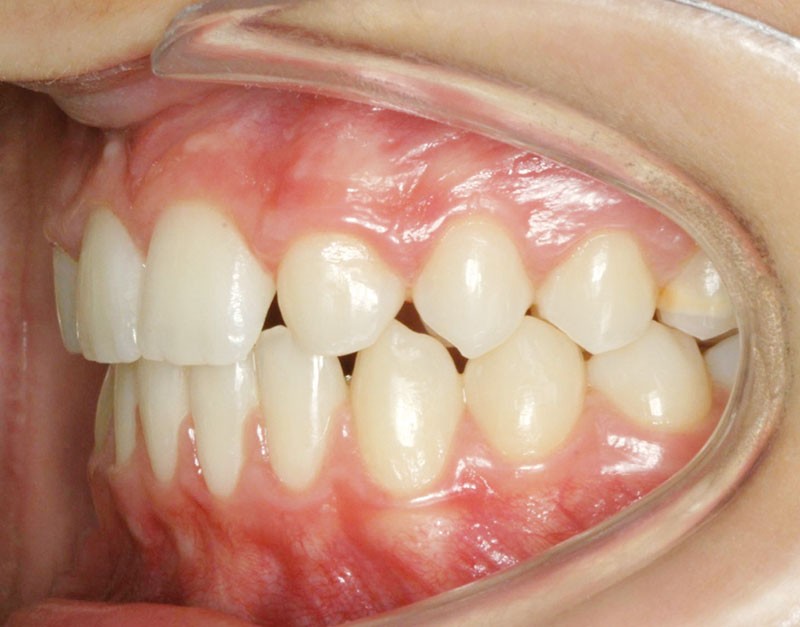

Les vues endo-buccales après extraction de 52 montrent des relations occlusales de classe II, un léger encombrement incisif mandibulaire et une tendance à la fermeture spontanée des espaces des incisives latérales confirmant le choix thérapeutique d’une fermeture d’espace (fig. 2).